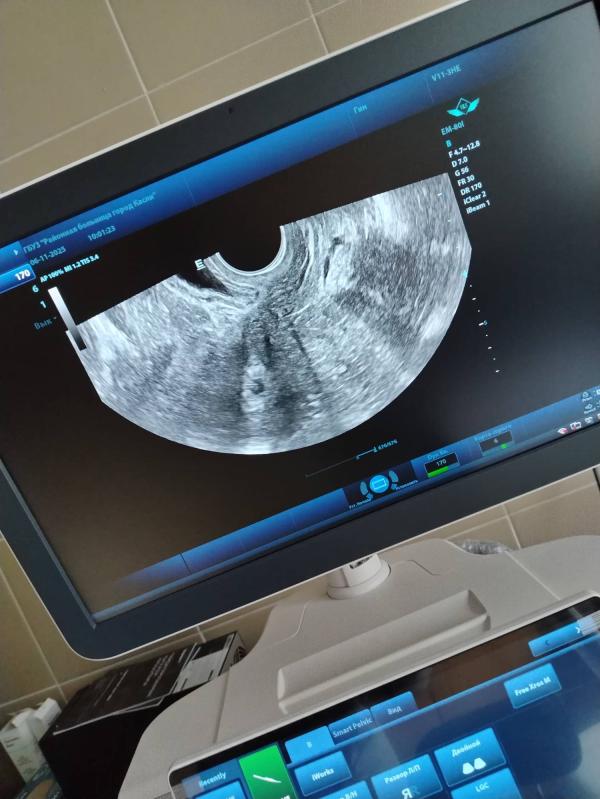

Увидела сегодня свое «колечко с бриллиантом»

20 дпп, ПЯ 9мм, жм 3 мм. Один остался со мной ❤️